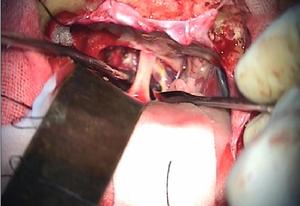

3.手術治療 微腺瘤,可經蝶竇手術治療,腺瘤超過10mm如有下述指征需經顱手術

(1)手術指征:①腫瘤向鞍上生長視神經交叉受壓下丘腦及第三腦室受壓引起腦積水等症狀者;②腫瘤向鞍前生長達到前顱凹額底者;③垂體卒中;④放射治療效果不滿意或惡化者;⑤有功能性或無功能性腺瘤產生臨床垂體功能亢進或減退者

(3)圍術期處理:垂體瘤術後內科併發症可有尿崩症全垂體功能減退代謝紊亂心功能不全和胃腸道出血因此手術前後的內科處理十分重要。內科處理有:手術前後的激素替代療法術後尿崩症的處理,水、電解質糖代謝的平衡,預防感染等。